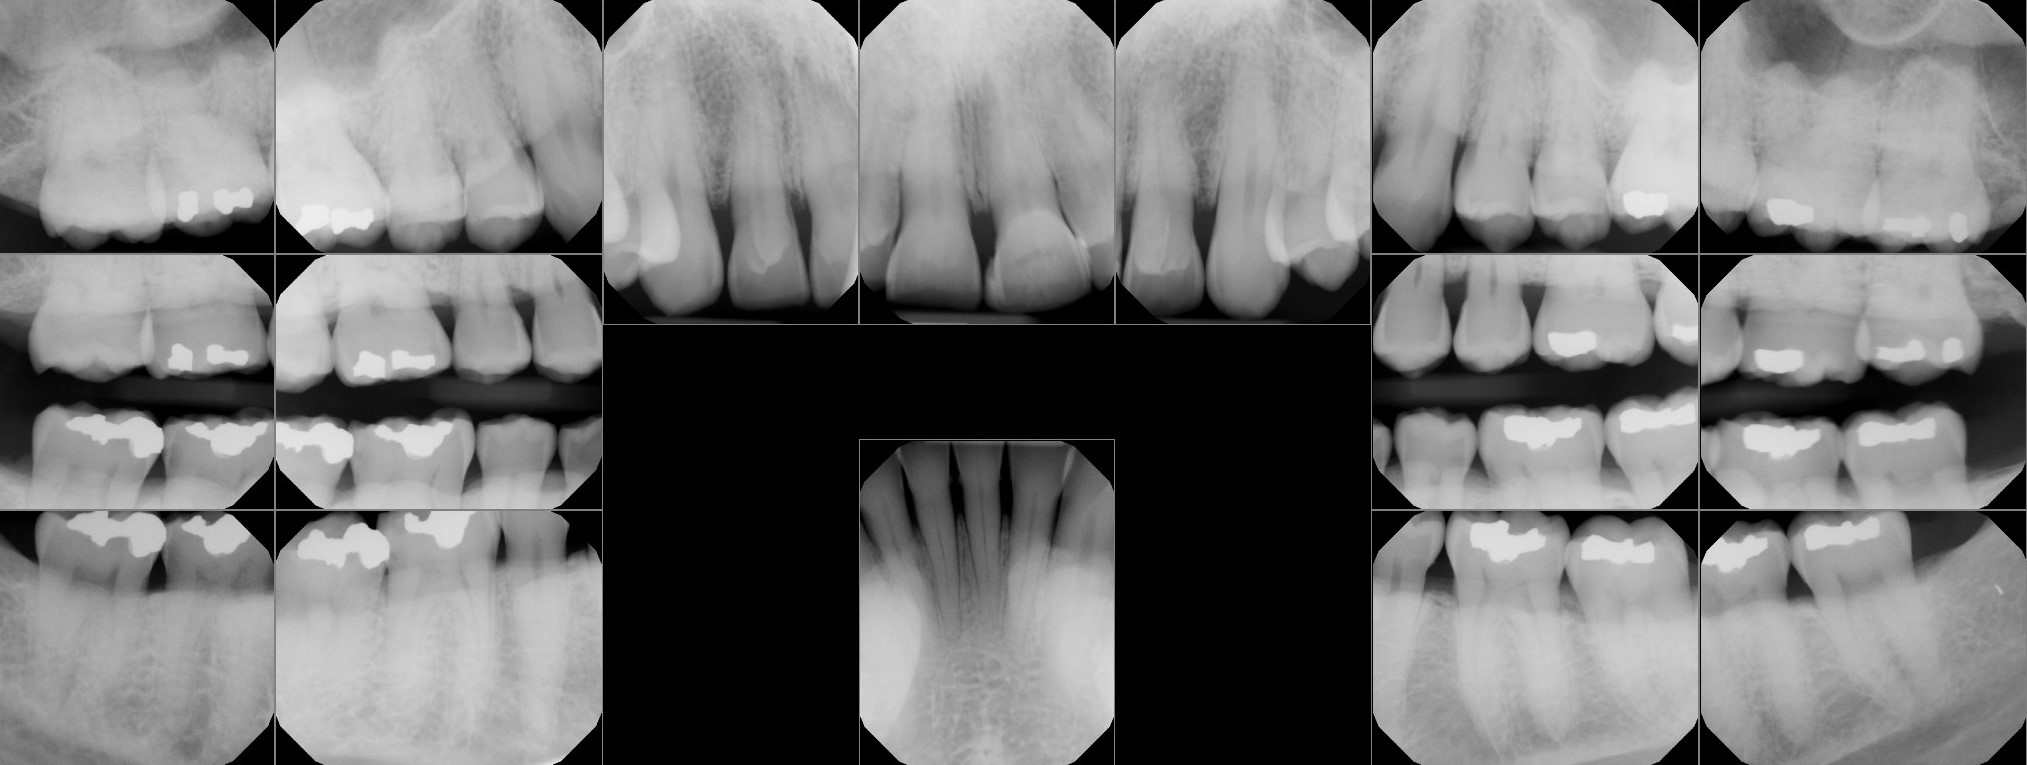

Patient needs crown on #31. Also needs full mouth scaling and root planing. Was quoted $1400 for the crown, was not told he needed buildup. X-rays attached.

Auction images